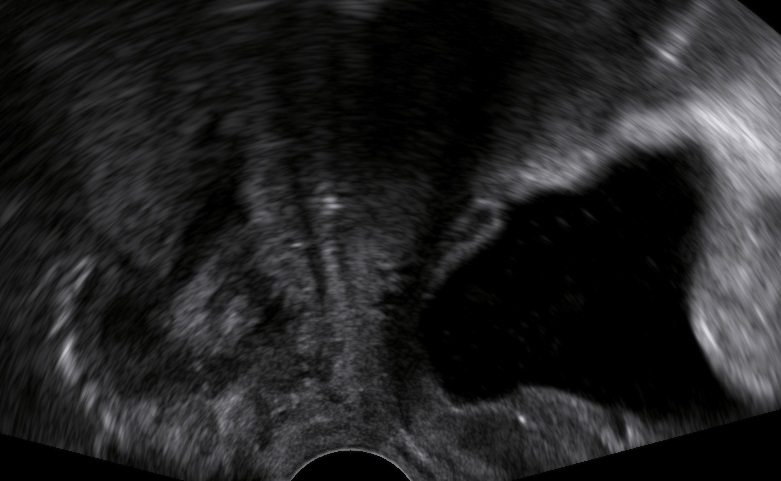

An 80-year-old female patient presents with persisting overactive bladder symptoms. After careful ultrasound examination, a unilocular cystic mass with a single urethral connecting tract containing a calculus was identified as an urethral diverticulum.

Clinical Image